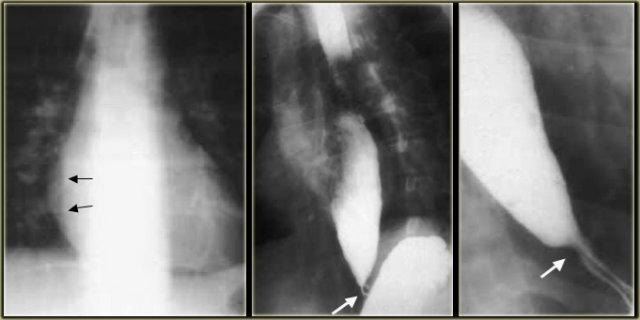

TRÁI: Thực quản giãn (mũi tên) biểu hiện là cấu trúc dài, bờ rõ nét song song với tim. PHẢI: Thực quản giãn thường lệch sang phải. Hẹp (mũi tên) tại khe hoành.

Achalasia

Hình ảnh chụp thực quản:

- Giãn thực quản kèm mất nhu động

- Hẹp thuôn nhẵn tại khe thực quản của cơ hoành

- Ung thư đoạn xa có thể giả dạng achalasia (giả achalasia)

TRÁI: CT cho thấy thực quản giãn (mũi tên) dẫn đến chỉ định chụp thực quản. PHẢI: Chụp thực quản cho thấy hẹp (mũi tên) tại mức khe hoành.

Bên trái là một bệnh nhân khác bị achalasia.

TRÁI: Thực quản giãn (mũi tên) được chiếu phía sau nhĩ phải. GIỮA và PHẢI: Hẹp thuôn nhẵn ngay trên cơ hoành (mũi tên).

Trong quá trình soi huỳnh quang, quan sát thấy một số nhu động với hình ảnh hẹp thuôn nhẵn điển hình ngay trên cơ hoành (mũi tên).